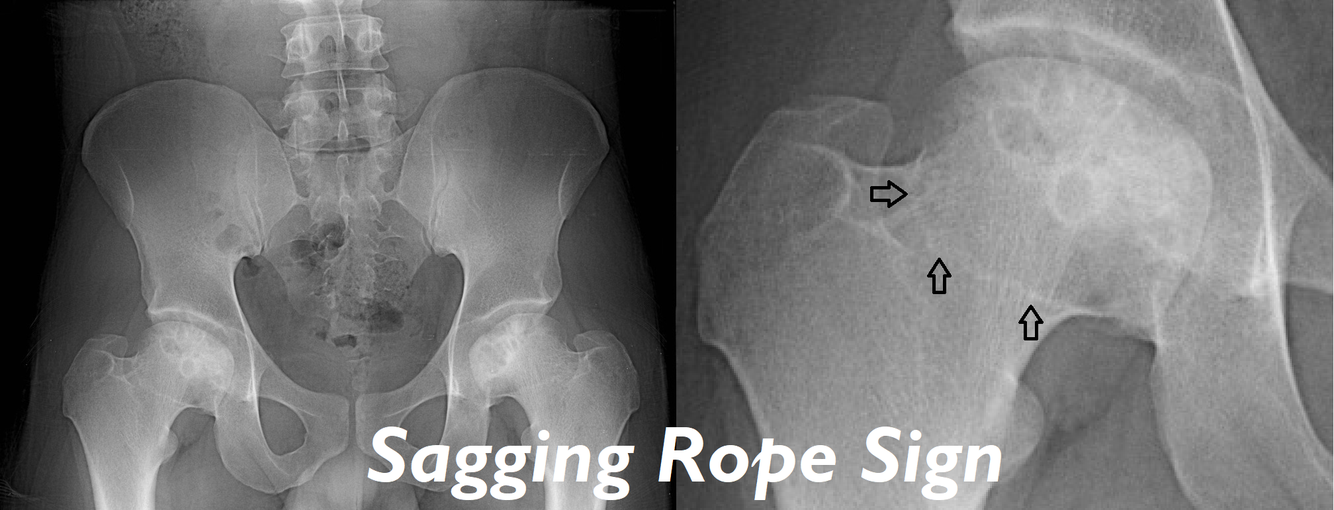

Later cases of AVN show changes on X-ray, what are these changes (before collapse)?